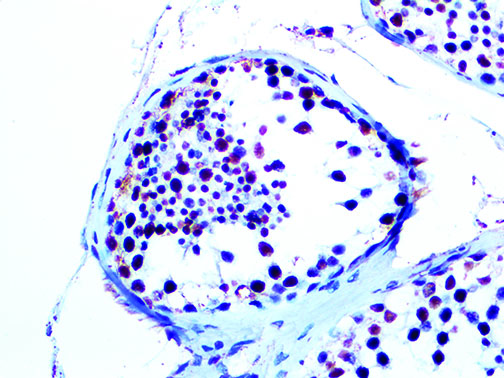

It is the ICU physician who is most likely to witness one of the deadliest manifestations of the abnormal immunological response, the cytokine storm syndrome (CSS). This response is also referred to by some as the cytokine release syndrome (CRS). CSS is characterized by continuous activation and expansion of macrophage and lymphocyte populations, which secrete large amounts of cytokines, causing the cytokine storm. This massive cytokine release is akin to hemophagocytic lymphohistiocytosis (HLH) disease, a syndrome characterized by initial unchecked and persistent activation of cytotoxic T lymphocytes and NK cells.

Clinical and laboratory manifestations of HLH include fever, enlarged liver and/or spleen, neurologic dysfunction, coagulopathy, liver dysfunction, cytopenias (i.e., low levels of erythrocytes, leukocytes, and/or platelets), hypertriglyceridemia, hyperferritinemia, hemophagocytosis, and eventually diminished NK cell activity as the immune system becomes progressively paralyzed. HLH can be familial (primary HLH) or secondary to another disease process (sHLH), such as rheumatic disease, in which it is referred to as macrophage activation syndrome (MAS, characterized by elevated ferritin).